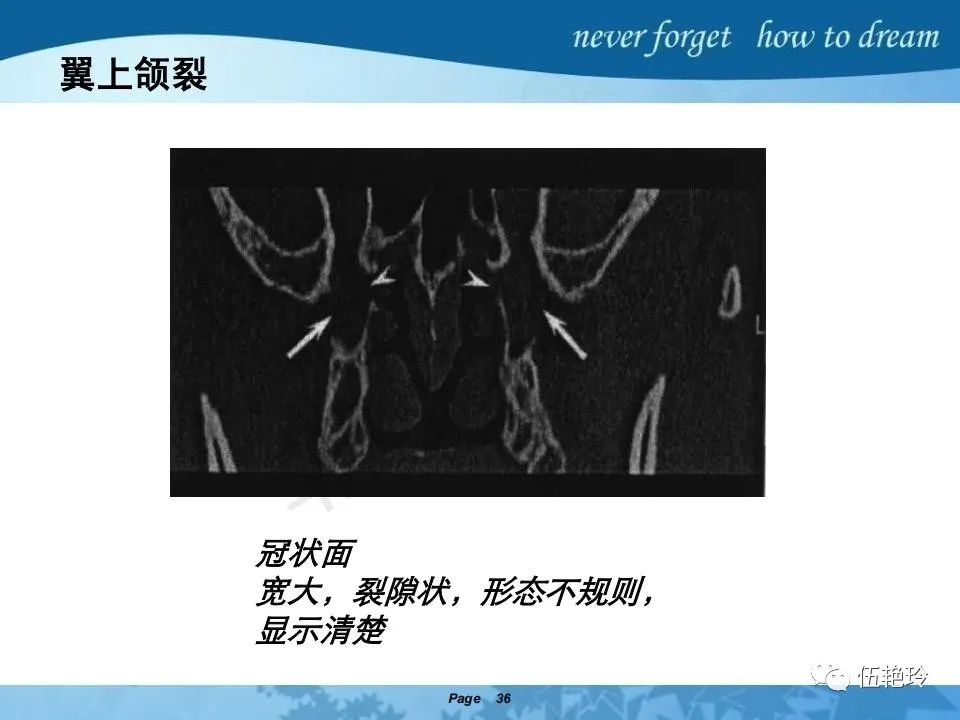

翼腭窝的解剖结构与鼻咽癌侵犯

颞下窝与咀嚼肌间隙